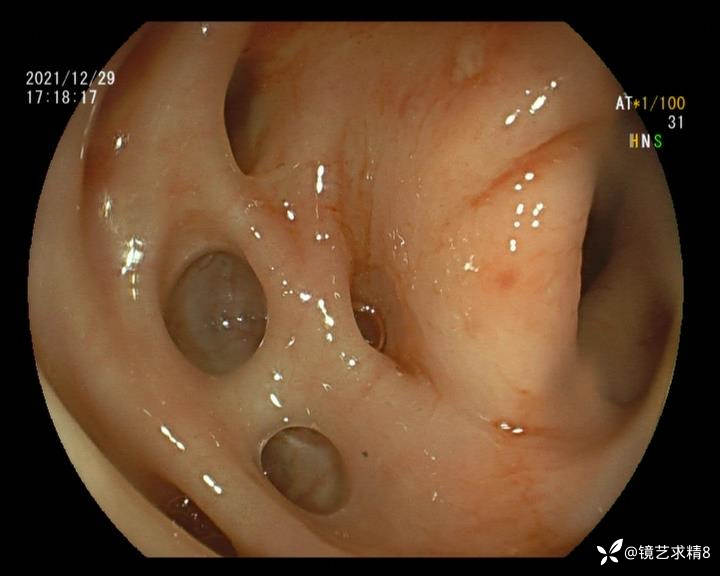

结肠内违建⥤结肠多发憩室☞续

小壮兵爱学习等 2人推荐看到手机存有2年前一个病例仅有的3张图片,因为没有更多的图片就只描述了多发憩室这个内容,没想到浏览量很快上万,很多都和我一样第一次见这么多憩室的结肠,就不得不想要把2年前所有的片子拷贝出来分享。该病例憩室合并外源性因素成为憩室出血的原因。后面附有代表性的全结肠图片。

患者以消化道出血入院,胃镜未见异常,肠镜进入乙状结肠就看到很多憩室,同时还看到肠腔用清肠药后移动下来1枚尖锐的枣核,这么多憩室,这个枣核扎入憩室的机会非常大,推测应该是掉入一坑🕳就算出来还会有很多坑🕳🕳🕳等着,掉入憩室内很容易刺破血管,这可能就是消化道出血的原因,继续前进可以看到有一些憩室内翻,还有一些息肉,问题来了,那么多憩室,犯罪分子是抓住了,它在那些憩室内作过案?到达回盲部后挨个冲洗,但憩室大小又不足以把镜头进入憩室内观察,针对有血块的憩室冲洗后可疑出血的以夹子闭合或套扎,取出枣核,如果有锥形透明帽可能钻入憩室精准电凝效果更好,若内镜下操作失败介入治疗成功率更高,经内镜下治疗后观察未再出血出院。